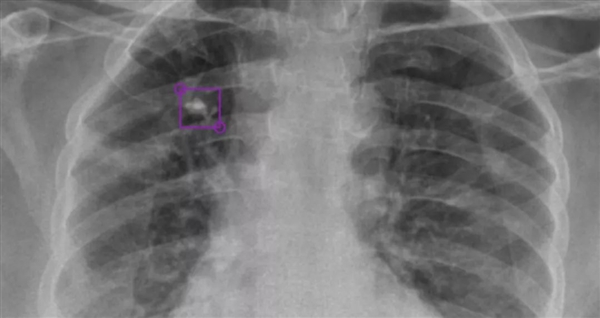

DeepTek AI模型檢測到的右上葉肺部鈣化結(jié)節(jié)

DeepTek希望通過AI驅(qū)動(dòng)的放射平臺(tái),大大提升全球在醫(yī)學(xué)影像診斷領(lǐng)域的能力,為此開發(fā)了全新的DxTB工具,用來篩查肺結(jié)核的X射線圖像,并標(biāo)記病例,以供醫(yī)學(xué)專家進(jìn)行優(yōu)先檢查。